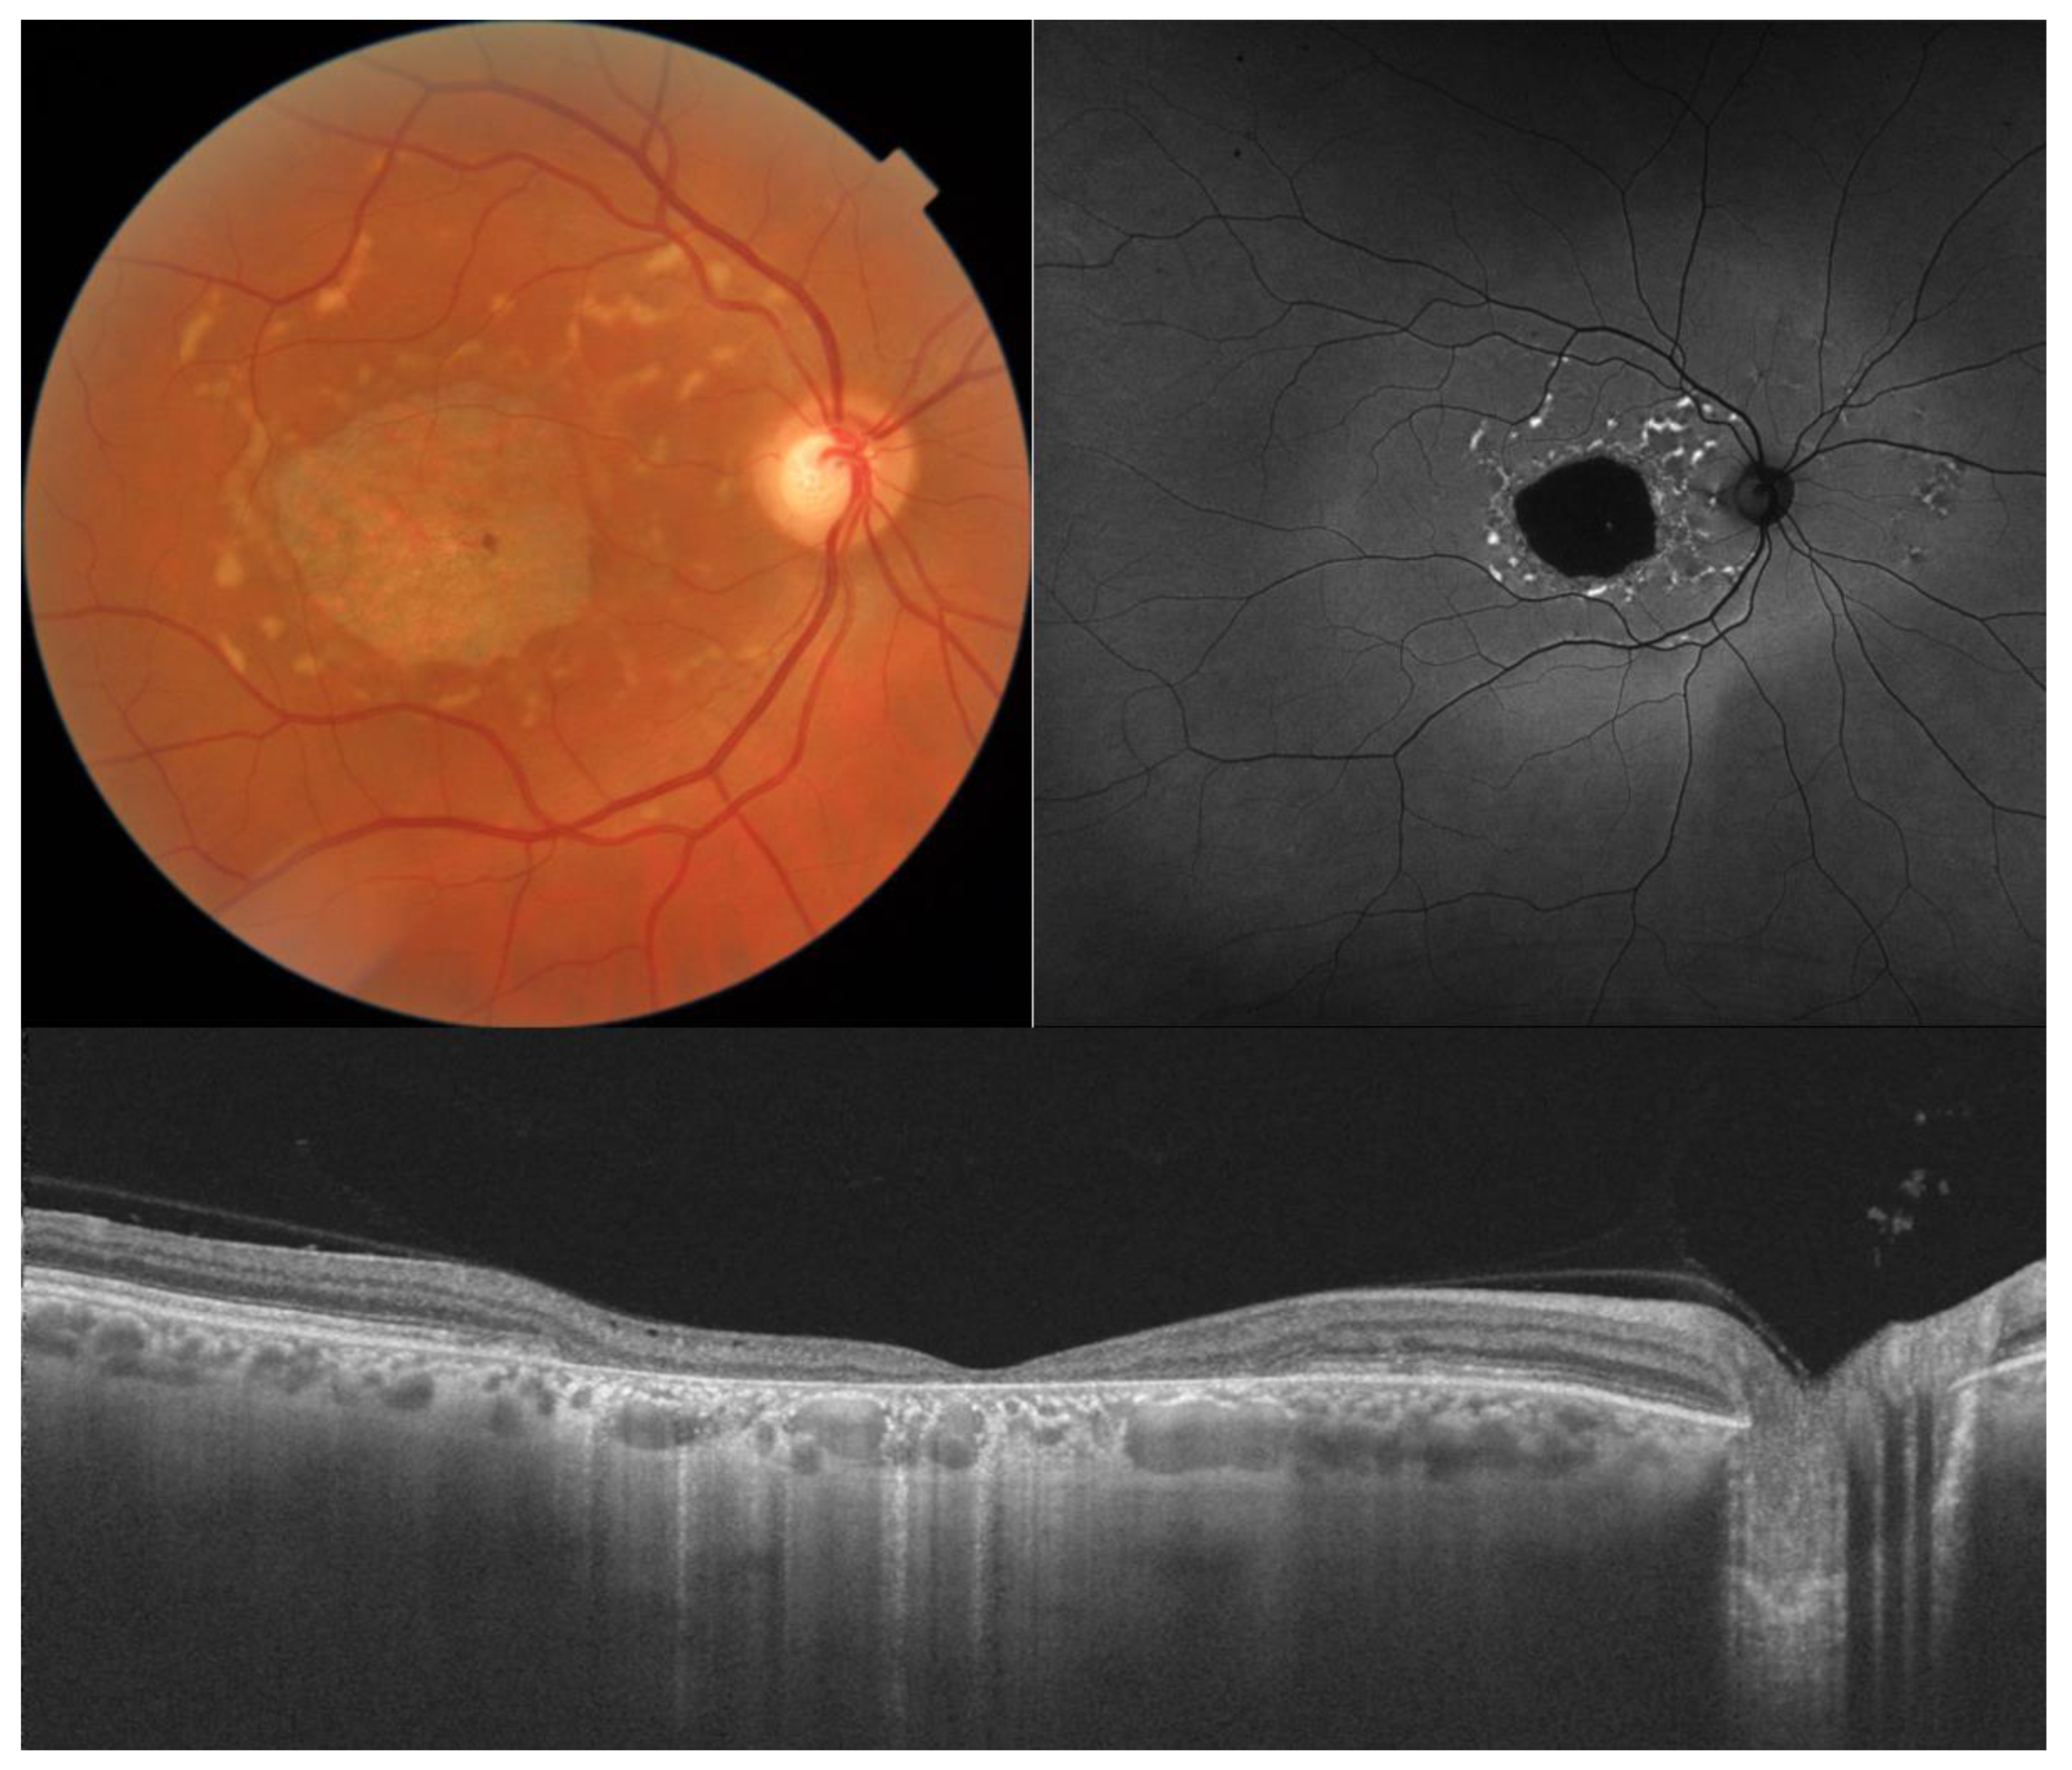

2. Stargardt Disease

| Stargardt disease |

|